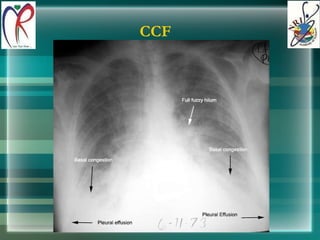

CCF